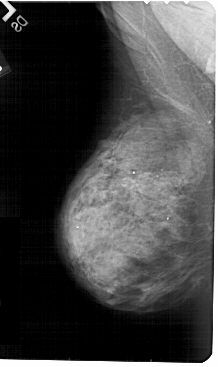

A_1810_1.RIGHT_MLO

RIGHT_MLO LINES 5491 PIXELS_PER_LINE 2926 BITS_PER_PIXEL 12 RESOLUTION 43.5 OVERLAY